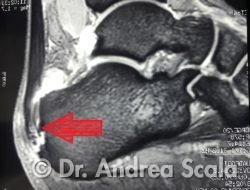

La Risonanza Magnetica conferma la presenza di una forte infiammazione della borsa retro achillea.

La Risonanza accerta che l’infiammazione dell’inserzione del tendine d’achille si accompagna alla presenza di frammenti ossei.